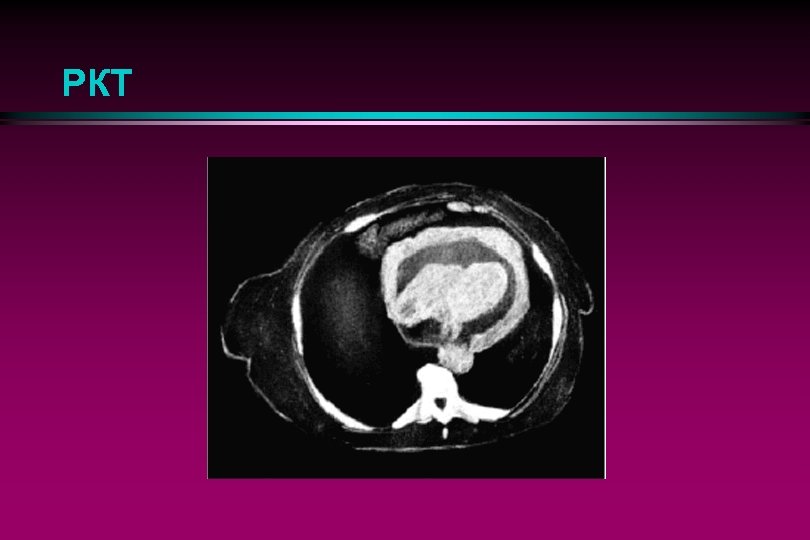

РКТ